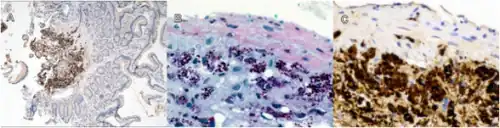

While T. whipplei is categorized with the Gram-positive Actinomycetota, the organism is commonly found to be Gram-positive or Gram-indeterminate when stained in the laboratory.[2] Whipple himself probably observed the organisms as rod-shaped structures with silver stain in his original case.[4]